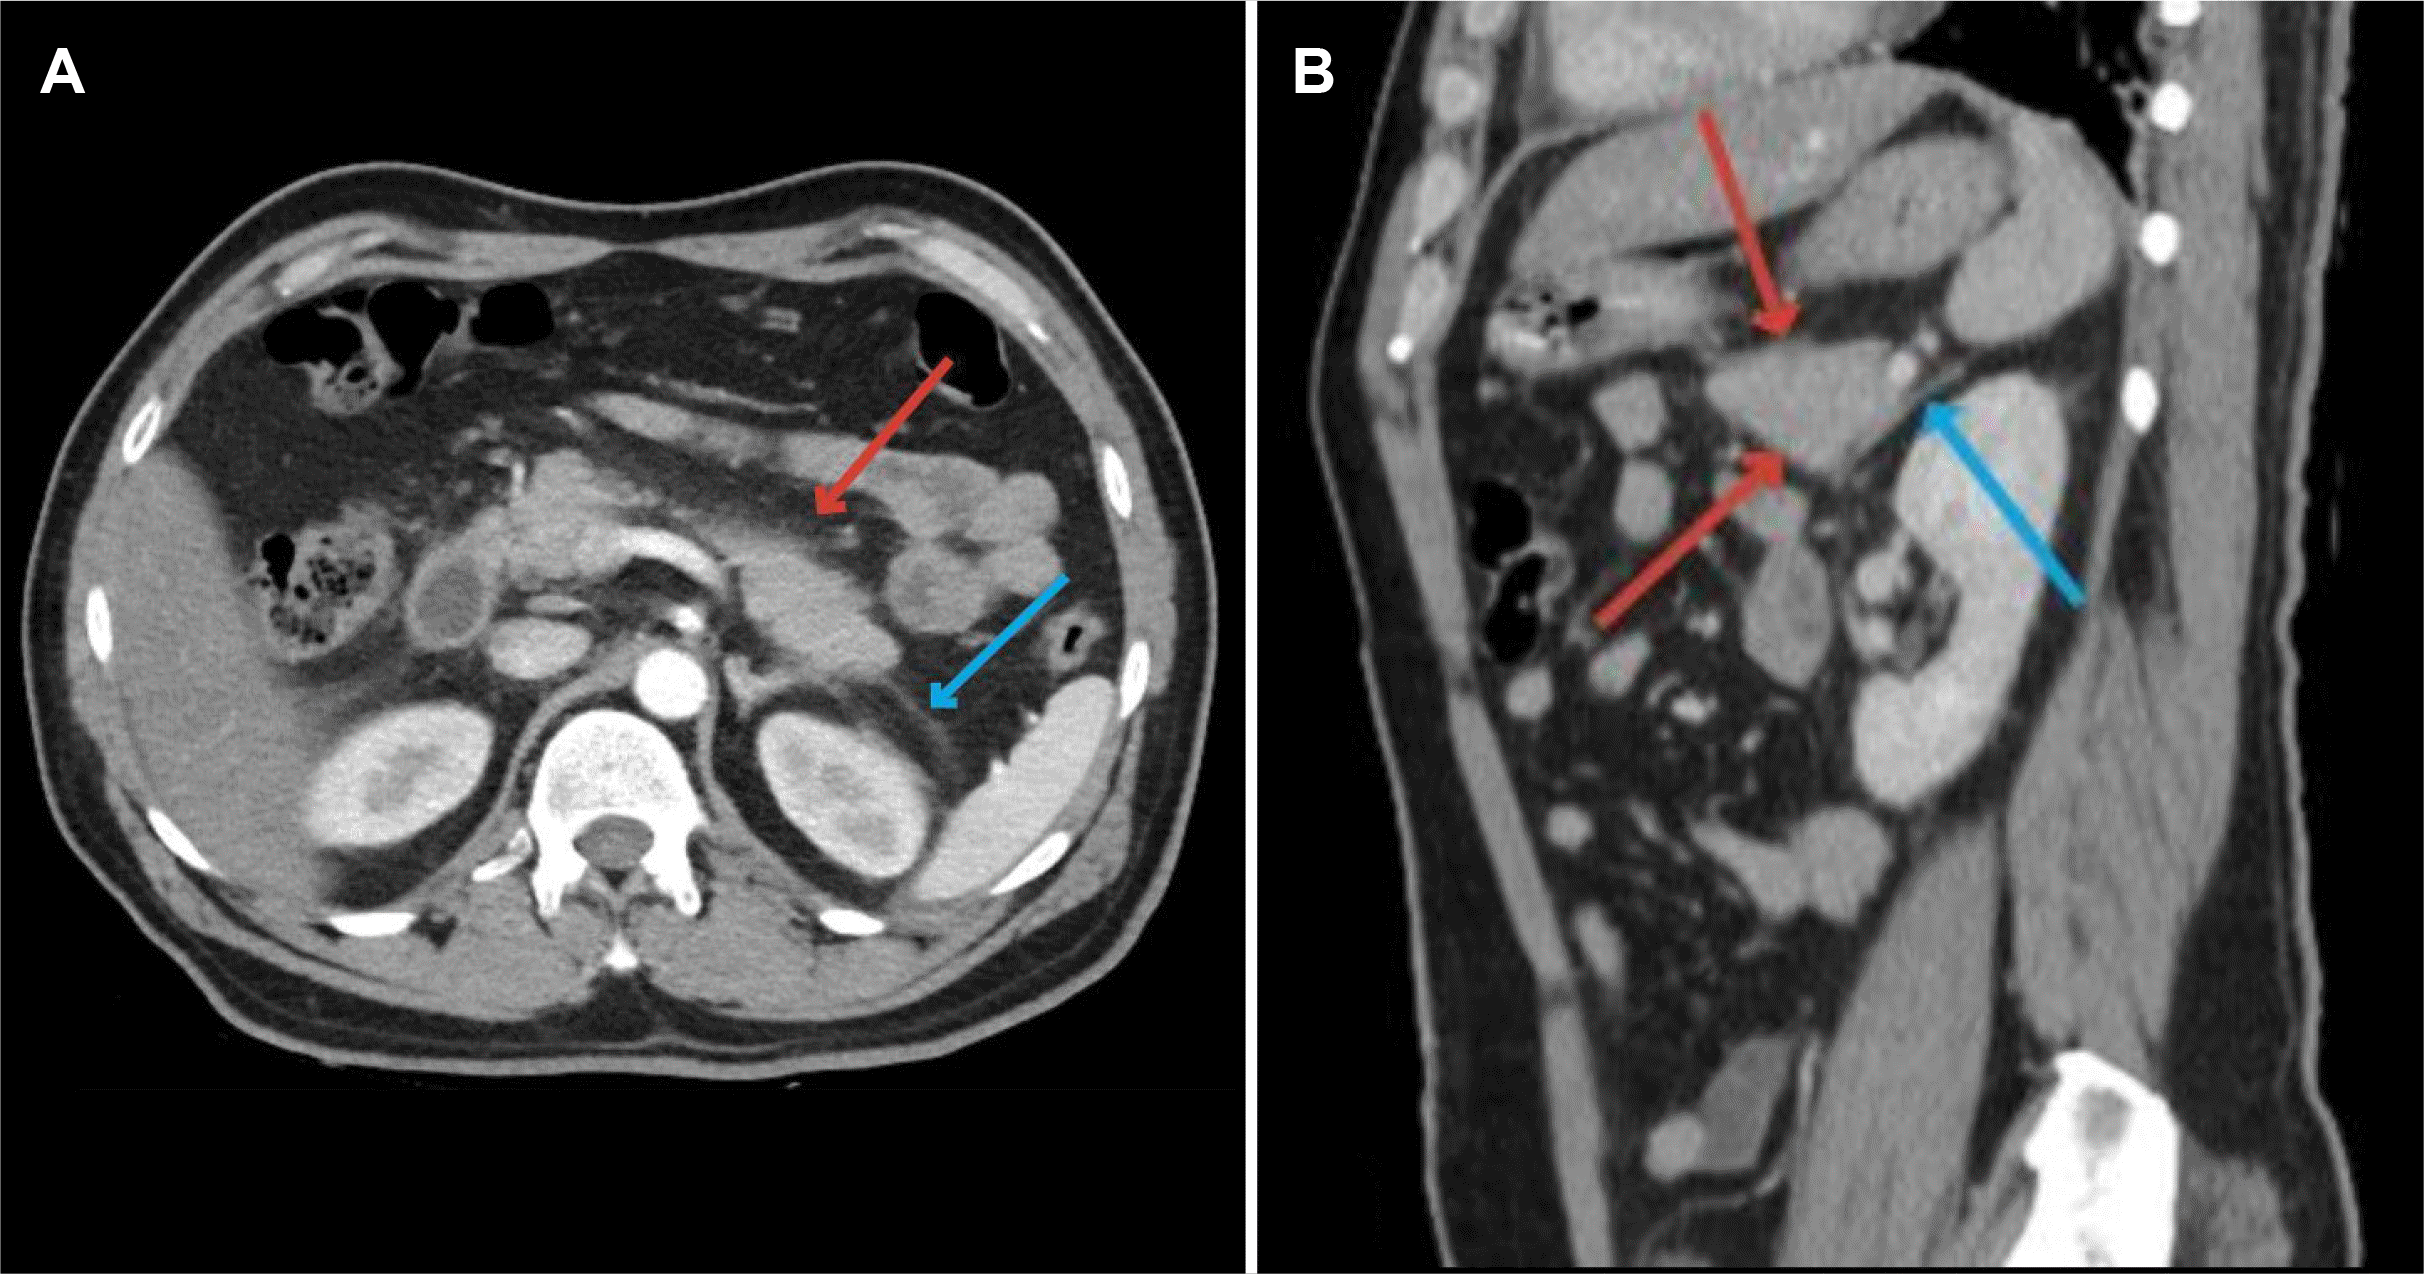

A computed tomography (CT) scan of the abdomen revealed findings consistent with non-necrotic acute pancreatitis with no demonstration of any mechanical obstruction of the biliary system (Fig. 1). Further laboratory workup revealed the following: hemoglobin, 7.1 g/dL; total leucocyte counts, 6.4×109 (total leucocyte counts 4.8–11.3); platelet counts, 10×109/L (154–433). More tests were ordered because of the bicytopenia, including iron 150 μg/dL, B12 321 pg/mL, retic count 4.50%, haptoglobin <0.01 g/L, Coombs negative, and lactate dehydrogenase (LDH) 987 I.U/L (120–256).

Fig. 1

(A) Computed tomography CT scan abdomen axial view–Minimal fat fuzziness is seen in the pancreatic location with peri-pancreatic fat stranding (red arrow) and mild thickening of the Gerota’s fascia bilaterally (blue arrow). These findings are consistent with acute pancreatitis. (B) CT scan abdomen sagittal view–Showing blurring of the outline of pancreatic clefts (red arrows). Mild thickening of the Gerota’s fascia bilaterally (blue arrow). These findings are also consistent with acute pancreatitis.

kjg-85-1-73-f1.tif